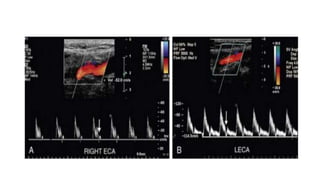

• The ECA, which supplies the muscular bed of the scalp, typically

demonstrates completely absent or very low velocity end-diastolic flow.

Although the amount of diastolic flow in the ECA may vary from patient

to patient, it should be symmetric right to left and less than the diastolic

flow in the ICA or CCA.

• An early diastolic notch followed by a short reversal of flow in early

diastole is often seen in the ECA.

PSV-131CM/SEC PSV-190CM/SEC PSV-266CM/SEC

• #30 The angle of spectral Doppler insonation should be kept between 45 and 60 degrees to minimize error in the calculation of velocity from the Doppler frequency shift. When the Doppler angle (yellow circles) is 44 degrees (A), PSV is calculated at 131 cm/sec. However, with a Doppler angle of 60 degrees (B), PSV is 190 cm/sec; and when the Doppler angle is 70 degrees (C), PSV is calculated at 266 cm/sec. Thus, an incorrect Doppler angle or variations in Doppler angle from examination to examination can introduce significant error into the measurement of PSV.